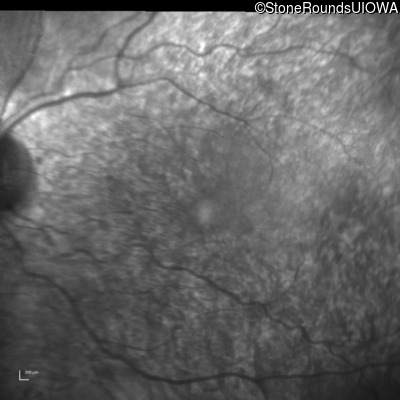

Infrared Fundus Photograph - Right - 20/100

Exemplar